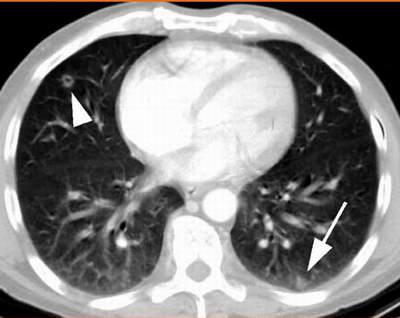

Tổn thương phổi do nấm trên phim chụp cắt lớp.